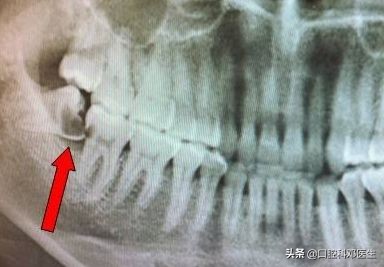

智齿是人类正常的牙齿,随着人类的进化,人从爬行到站立,从生食到熟食,从粗粮到细粮,其中骨头、牙齿、肌肉的进化不完全同步,脸蛋越来越小,导致骨量与牙量不协调,骨头内不能容纳更多的牙齿,特别是最后萌出的智齿。

智齿没有足够的空间萌出,只能部分萌出,或者完全埋伏在骨头内,这就为智齿发炎留下了病根,只要抵抗力下降,就会引起细菌大量繁殖,引起智齿区域的疼痛。